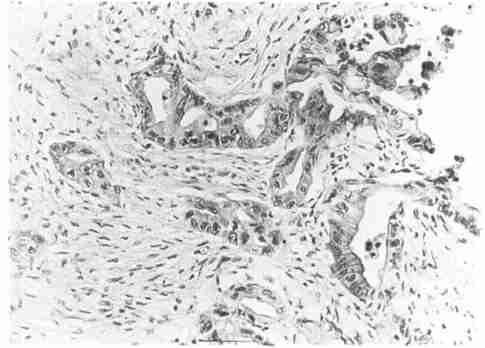

血管瘤多数为很小的息肉状肿物,突出或悬垂于肠腔内,亦可环绕肠管生长,呈红色或紫红色、柔软可压缩的肿物。多为单发,亦可为多发,呈局限性或弥漫性分布。肿瘤大小不一,可以小至1cm以内,大至侵犯一段肠袢超过30cm长度真性的血管瘤常是孤立界限清楚无包膜、由血管组成的肿块主要是毛细血管及薄壁的静脉,动脉亦可见。

肠血管瘤可以同时伴发其他脏器的血管瘤,例如食管、胃、小肠、口腔或咽喉部的血管瘤或皮肤乳头状瘤。组织病理学检查的典型表现为扩张增生的血管团。许多病变,尤其是比较大的病变内可见广泛分布的新鲜或陈旧的血栓,伴有黏膜下纤维化,并可在长期血栓的部位见到钙化。